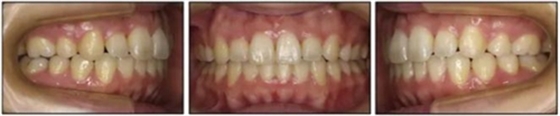

1.基本信息:女性,24歲2月,主訴上前牙及上唇不美觀(圖1)。因美觀問題不愿使用上頜固定矯治器。

2.檢查:凸面型、骨性II類,安氏II類1分類錯合畸形。面型正中對稱,下面高略高,頦部后縮,唇肌略緊張。無顳下頜關(guān)節(jié)癥狀,下頜運動正常,無偏斜。上下頜中線與面中線相一致,所有恒牙存在,口腔衛(wèi)生可,牙周情況可?;颊呓】?,無系統(tǒng)性疾病,無牙科創(chuàng)傷史及不良習(xí)慣,懷疑遺傳因素導(dǎo)致錯合畸形。

3.測量分析:治療前記錄提示該患者左右磨牙與尖牙為安氏II類關(guān)系,上頜牙弓重度擁擠,下頜牙弓輕度擁擠,深Spee曲線。6.3mm深覆蓋,80%深覆合。牙齒無齲,無第三磨牙。